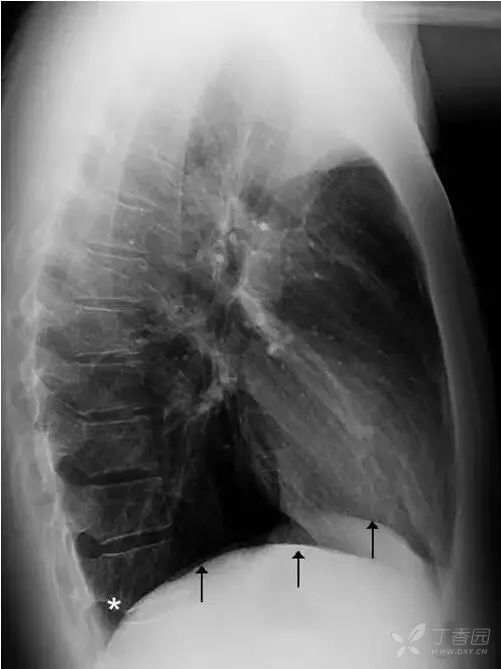

横膈分隔胸、腹腔,呈圆顶状。通常左侧横膈略低,右侧横膈略高,相差约1~2 cm。正位胸片上横膈(图17)内侧与心脏形成心膈角,外侧与胸壁形成肋骨角。

正常情况下,肋膈角是锐利的锐角。侧位胸片上(图18),横膈与前、后胸壁间分别形成前、后肋膈角。后肋膈角通常也是锐角,其位置在站立位为全肺最低处。

图17 正位胸片上两侧横膈呈圆顶状(黑色箭头),白色星号标示两侧肋膈角,正常情况下为锐角。

图18 侧位胸片上两侧横膈(黑色箭头)及后肋膈角(白色星号)。